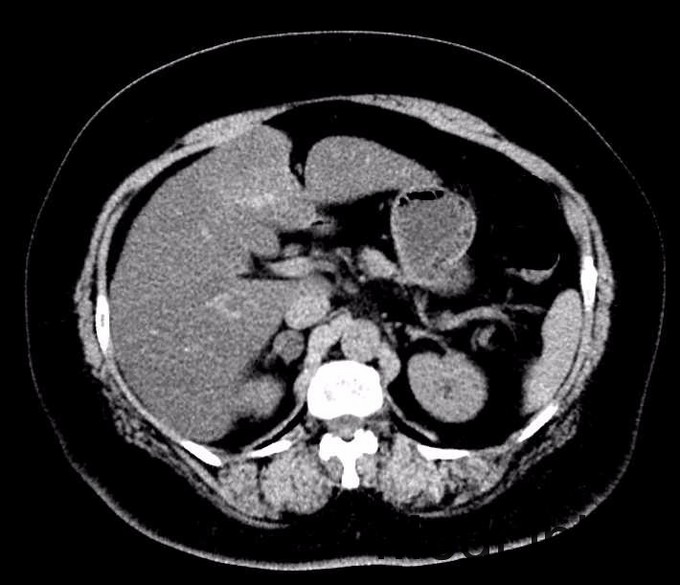

患者女,62岁,主因“发现膀胱肿物3年余” 患者3年前运动后出现右侧腰部疼痛,休息后自行缓解,于当地医院行泌尿系B超提示膀胱肿物(大小不详),偶有尿痛、排尿困难,无明显尿频、夜尿增多,无肉眼血尿,无腰痛、发热。于昌平医院行膀胱肿物电切除术,后行多次化疗。3年内定期复查,2015年9月泌尿系B超提示:膀胱内壁两处实性小结节,大小分别为0.5*0.4cm,0.4*0.3cm。建议手术治疗

膀胱彩超(2015-9-14 北京昌平区医院)示:膀胱充盈尚好,右侧壁探及两处偏强回声凸起,大小分别约0.5*0.4cm,0.4*0.3cm